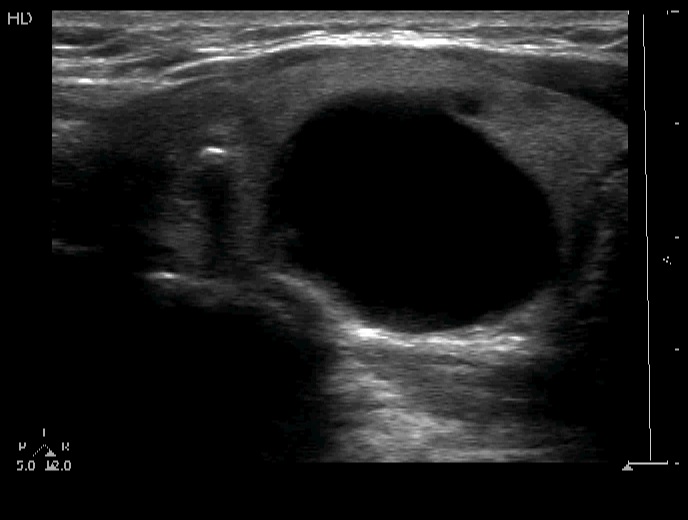

Follicular adenoma (histological diagnosis)

Before aspiration

After aspiration 6.5 ml cystic fluid

The granules in the solid part lower to the cystic area are punctate echogenic foci (microcalcifications).